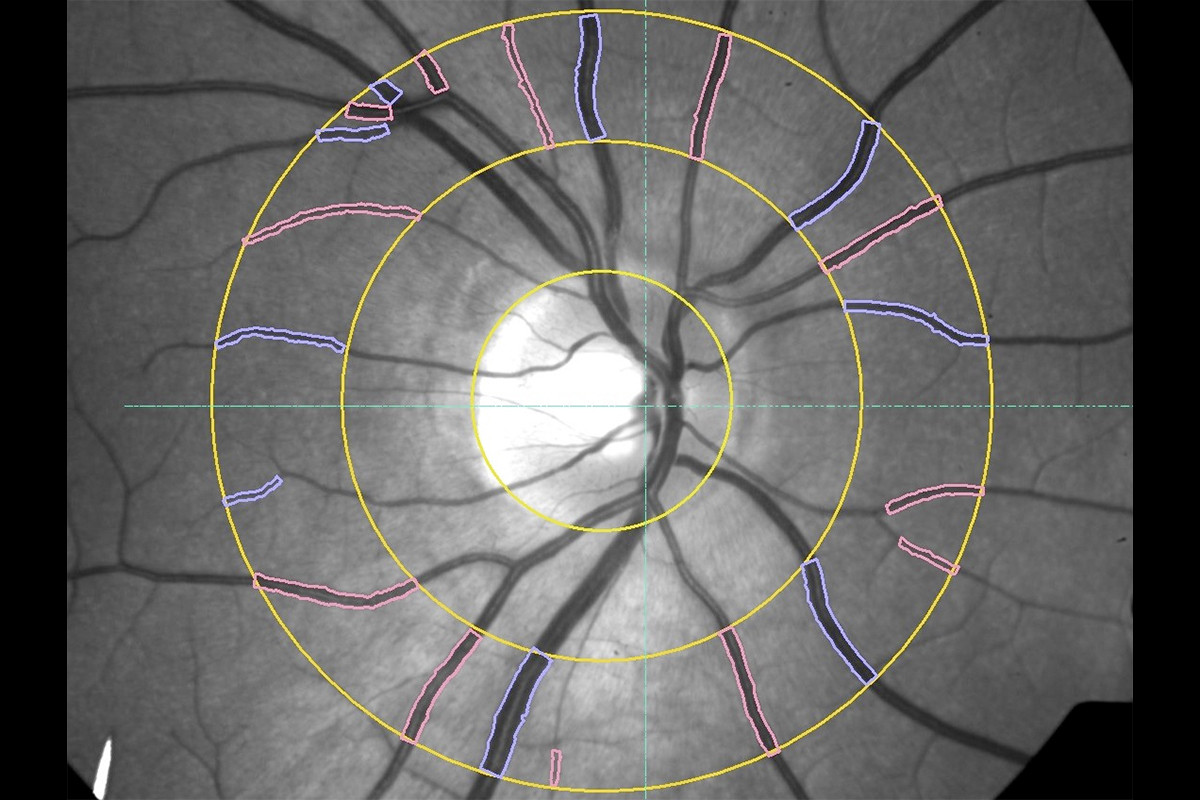

VesselMap aric: Image of the ocular fundus with measuring rangeVesselMap aric: Image of the ocular fundus with measuring range

2. The fundus image is opened in the software and the papilla is marked. Therefore, a measurement grid is placed on the image.

3. Subsequently, within this measurement grid (ring zone), all essential arterial and venous vessels are marked manually by selecting and clicking on them.

4. The software now determines the vessel diameters according to the marked vessels and calculates the static vessel parameters.

The static vessel parameters include:

• Central retinal arteriolar equivalent (CRAE): arterial model vessel diameter

• Central retinal venular equivalent (CRVE): venous model vessel diameter

• Arteriolar-to-venular ratio (AVR): CRAE/CRVE ratio